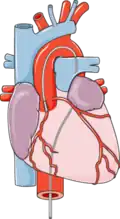

Perkutánní koronární intervence (PCI), dříve označovaná jako angioplastika koronárních cév (PCTA) obvykle přímo navazuje na koronarografické vyšetření.[1][2][3] Katétr je zaveden vpichem do tepny v třísle nebo na zápěstí. Na rozdíl od jiných katetrizací srdce, perkutánní koronární intervence cíleně vstupuje do jednotlivých věnčitých tepen.

Postupně jsou sondovány a nastřikovány srdeční tepny

Postupně jsou sondovány a nastřikovány srdeční tepny -

Po nalezení zúženého místa je zaveden balonek, který pod přibližně megapascalovým tlakem rozšíří průsvit tepny

Po nalezení zúženého místa je zaveden balonek, který pod přibližně megapascalovým tlakem rozšíří průsvit tepny -

Intervence může být zakončena umístěním stentu

Intervence může být zakončena umístěním stentu -

V případě rozsáhlého zúžení tepen (které se nedá ošetřit katetrem) je nutné pacienta přeložit na kardiochirurgický sál, kde se provede operativní přemostění neprůchodné věnčité (koronární) tepny cévou pacienta - koronární bypass.